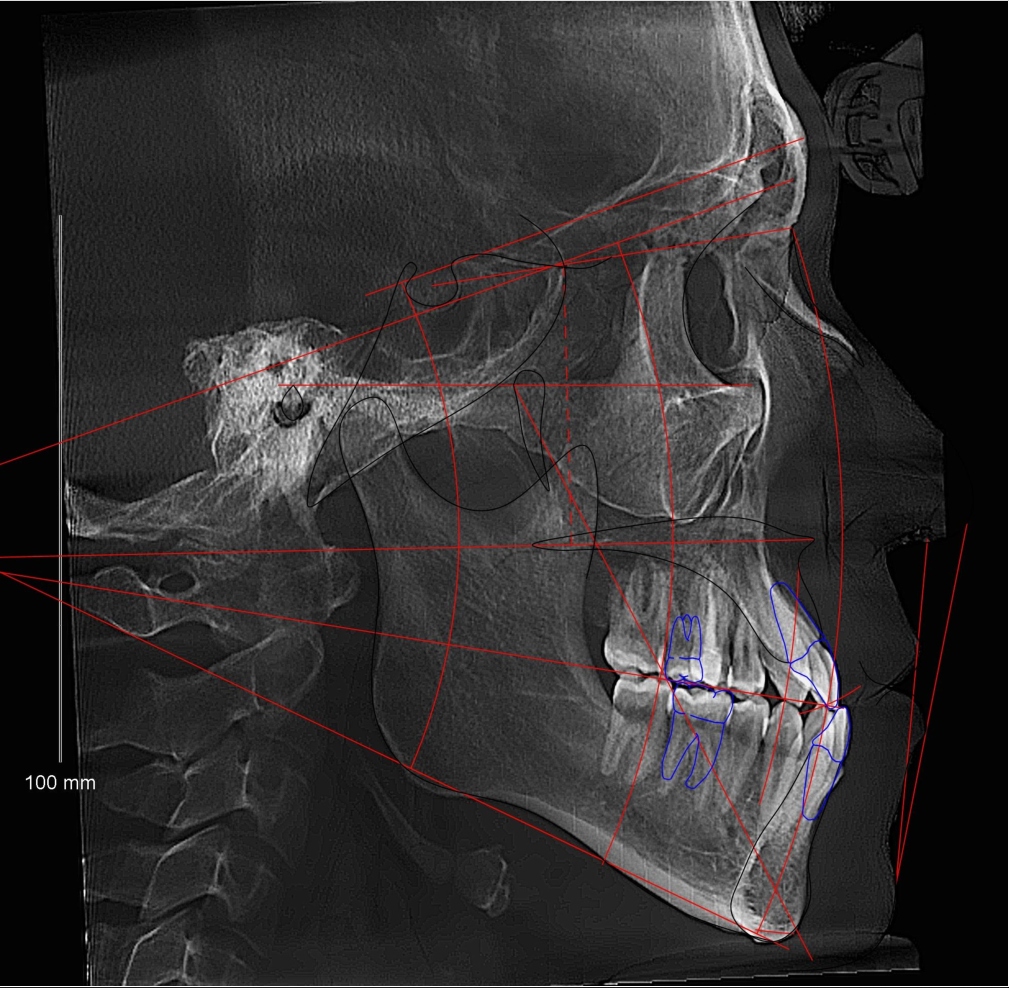

трг прав.jpg

ортодонт сказал пик 1 самое главное, от этого зависит можно ли просто вытянуть зубы брекетами не проебав шейки и дёсна